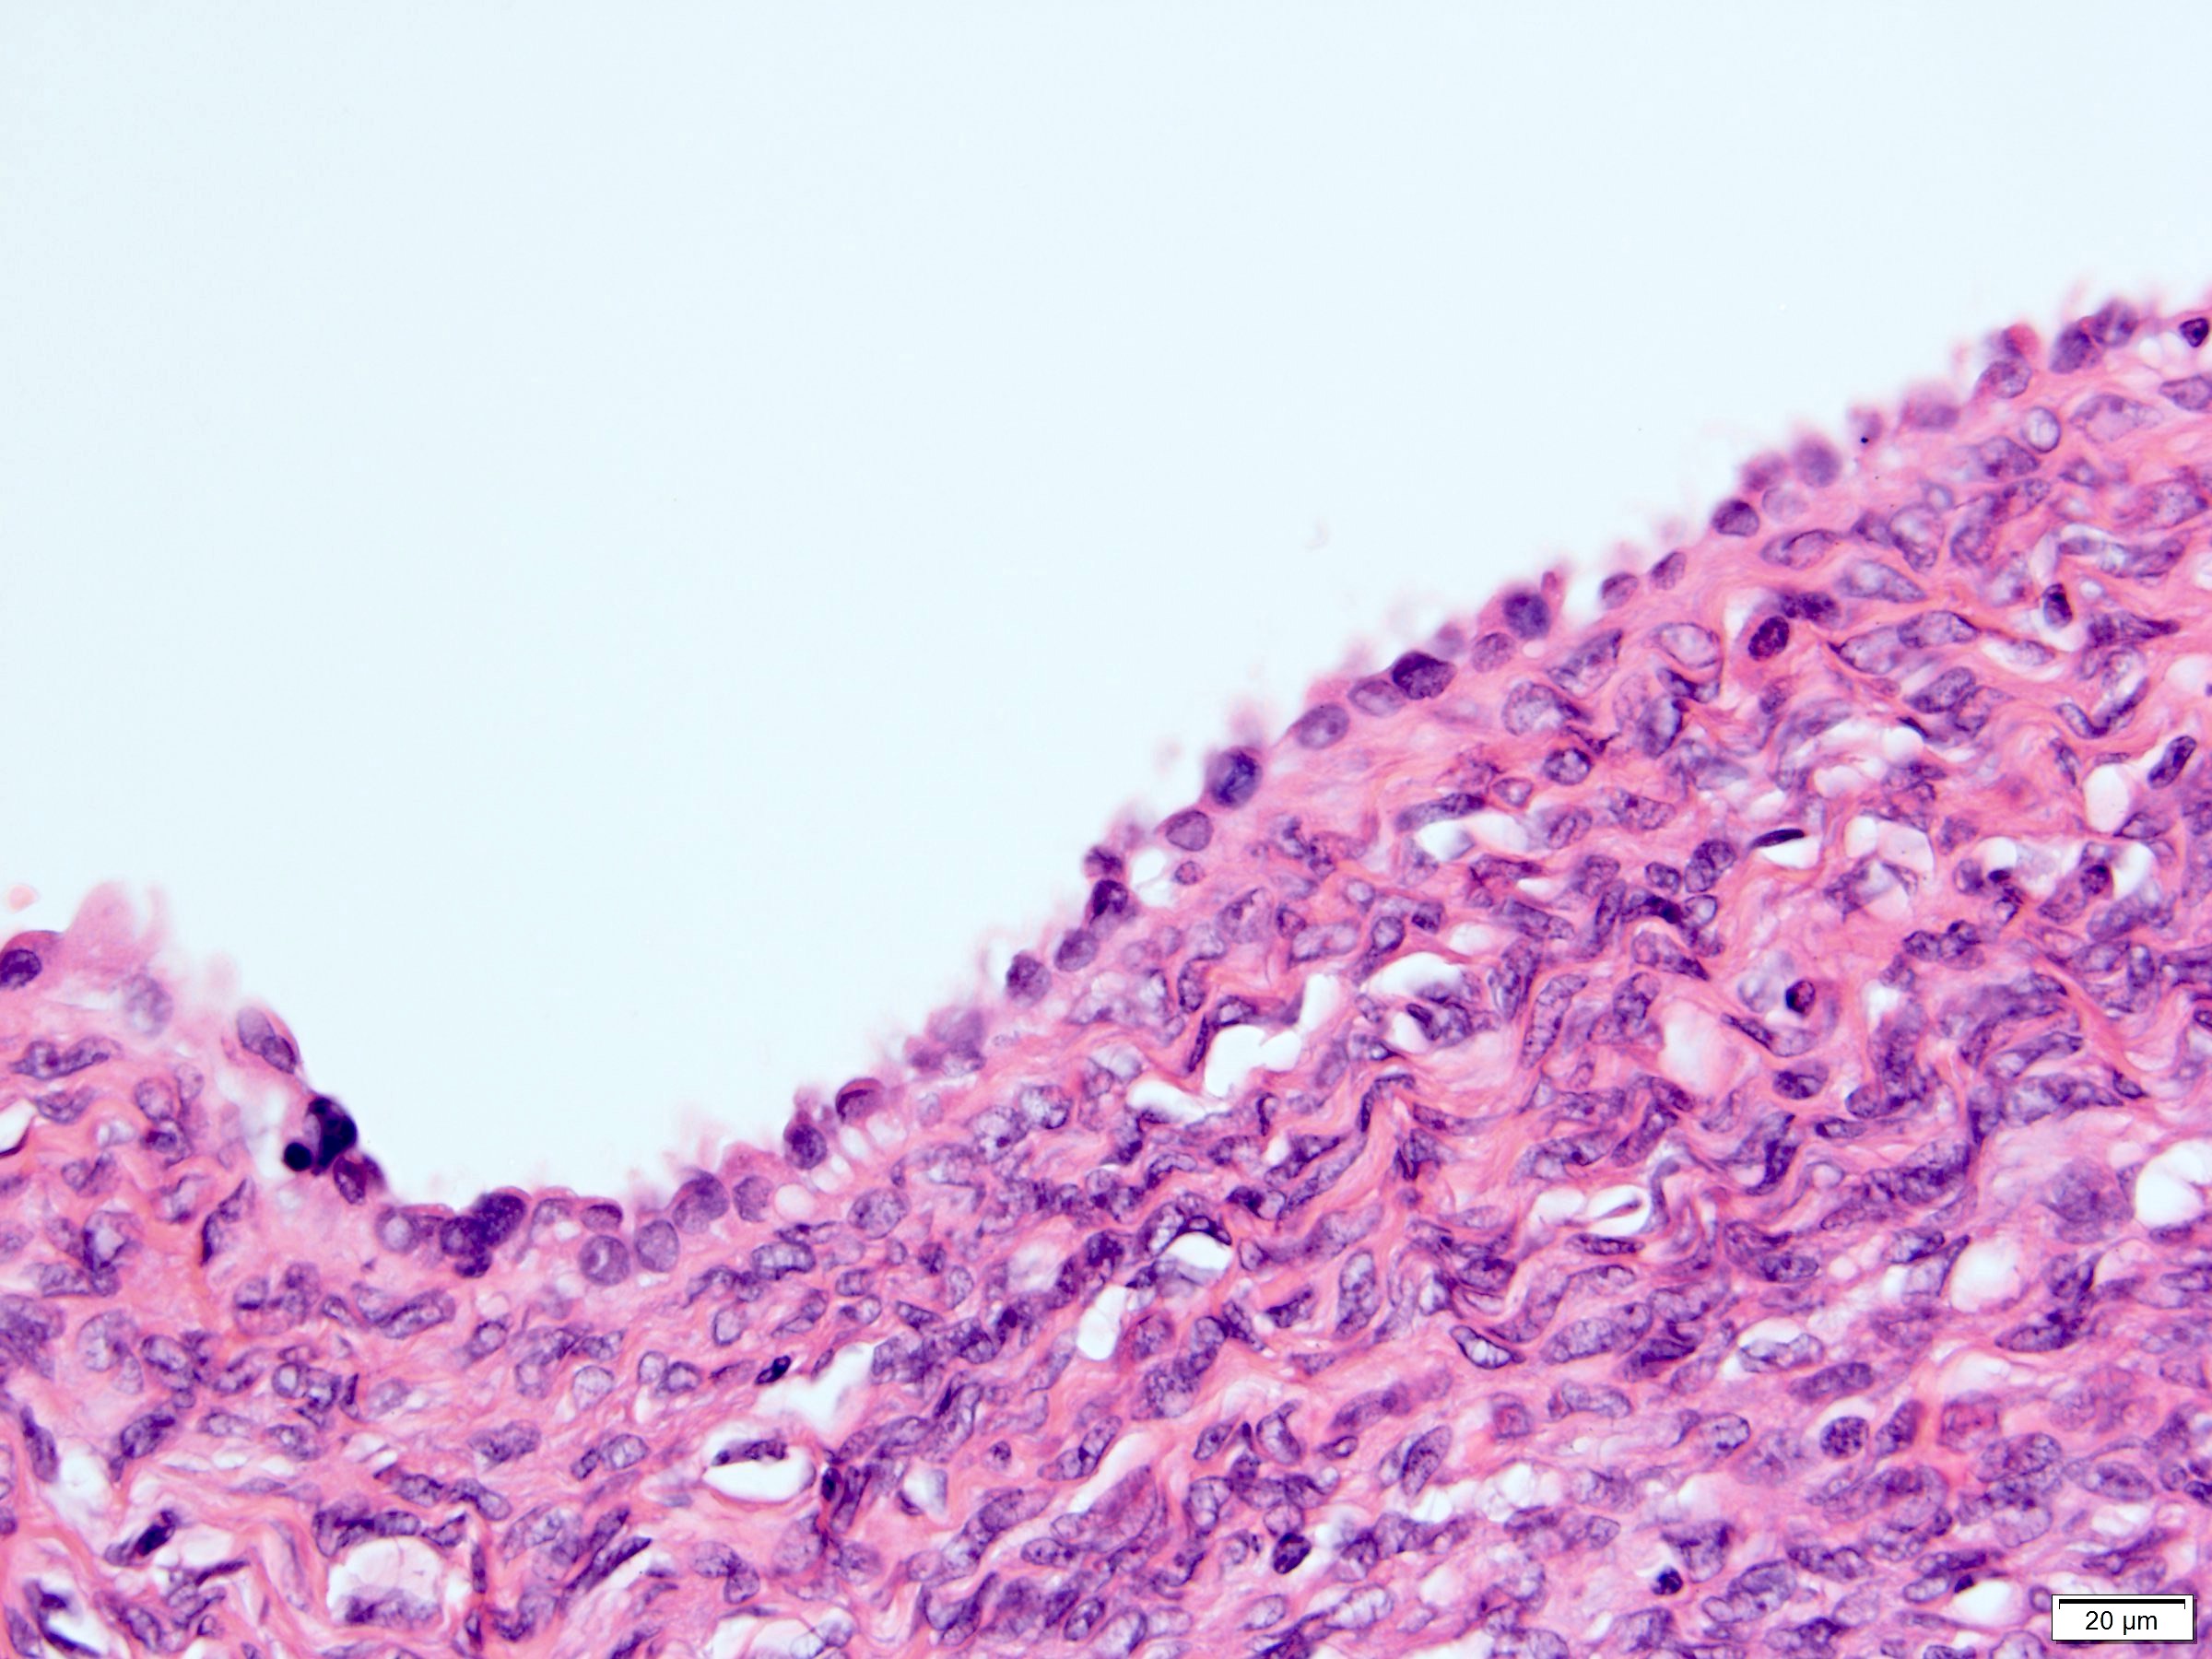

Microscopic (histologic) description

- Many with at least a partial pseudocapsule

- Entirely composed of cysts separated by septa (Semin Diagn Pathol 1998;15:2, Arch Pathol Lab Med 2004;128:1404, Am J Surg Pathol 2007;31:489, Eur Urol 2008;54:1237, Am J Surg Pathol 2016;40:1591)

- Stroma:

- Hypocellular to hypercellular

- Collagenous and fibrous to edematous and myxoid

- Areas of hyalinized stroma with contours resembling ovarian corpora albicantia

- Spindle cells; closely packed areas resemble ovarian stroma

- Cellular foci embedded with epithelial elements ranging from handful of cells with no lumen to tiny cysts with pinpoint lumens and to slightly larger cysts

- Steroidogenic cells: small clusters of polygonal cells with amphophilic cytoplasm and round nuclei, frequently around epithelial component

- Calcifications, multinucleated giant cells, foamy or hemosiderin laden macrophages and focal chronic inflammation

- Epithelium:

- Cells lining cysts

- Mostly arranged in single layer with various morphology: flat, cuboidal, hobnail, clear cell

- Rarely, foci of blunt and delicate papillae or foci of multiple layers of epithelium

- Minimal cytologic atypia

- Rare necrosis, no mitosis

Microscopic (histologic) images

A 6 cm predominantly well circumscribed, multicystic mass was incidentally found in a 55 year old woman. Sections of the partial nephrectomy showed the above histologic features. The stromal component is positive for ER and PR (shown above). What is the likely diagnosis?